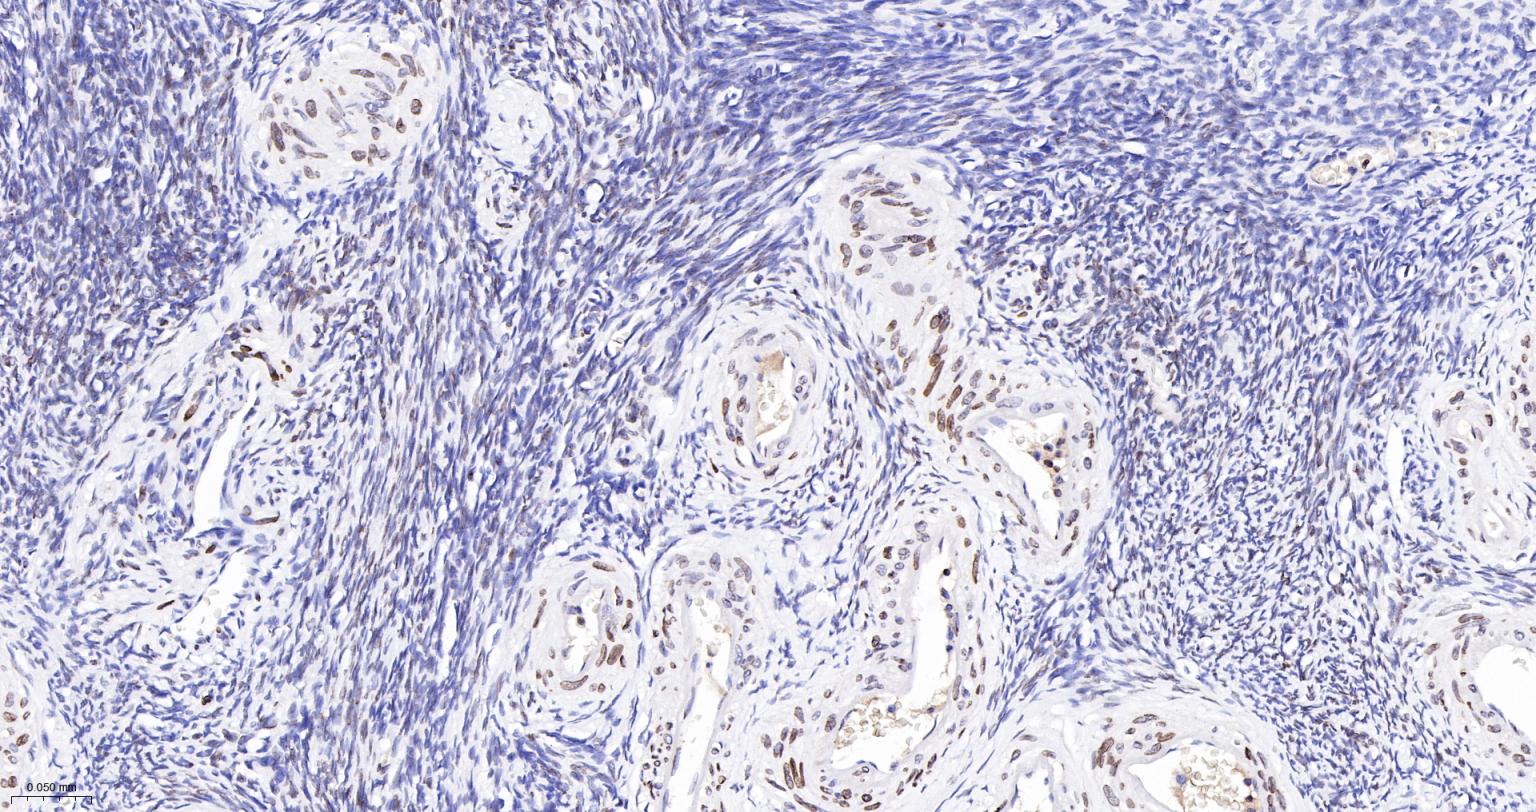

Paraformaldehyde-fixed, paraffin embedded Human Ovary; Antigen retrieval by boiling in sodium citrate buffer (pH6.0) for 15 min; The section was incubated with RAP80 Monoclonal Antibody, Unconjugated (bsm-61657R) at 1:200 overnight at 4°C, followed by conjugation to the bs-0295G-HRP and DAB (C-0010) staining.